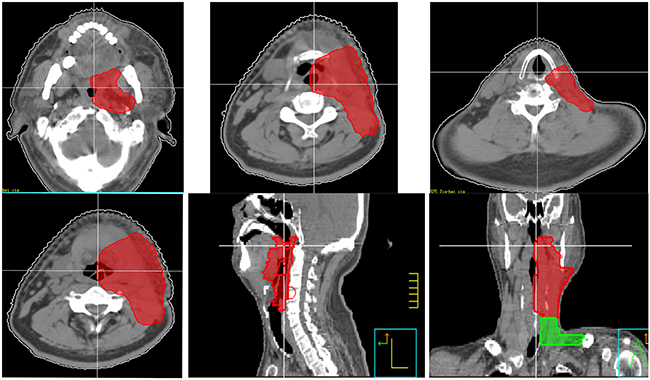

However, as for Group C and D, our retrospective data showed that there was a relative high incidence of primary emergence (14/46,30.%) and neck recurrence (14/46, 30%), which demand us to improve our treatment for these patients. In addition to neck irradiation, a relative comprehensive mucosal site should be included. Since 2014, we designed a new target volume (clinical target volume for mucosal site) delineation standard for these patients. The target volume including unilateral oropharynx, hypopharynx, supraglottic structures and unilateral neck, excluding oral cavity, vocal cord and cervical esophagus (Figure 3). We intend to decrease the mucosal failure as well as neck failure by this radiation field coverage, and preliminary results have been achieved.

Figure 3: New target volume delineation standard for non-NPC patients (clinical target volume for elective mucosal irradiation). The target volume including unilateral oropharynx, hypopharynx, supraglottic structures and unilateral neck, excluding oral cavity, vocal cord and cervical esophagus. For midline structures, such as base of tongue, soft palate and epiglottis, the target volume should include part of contralateral structures.